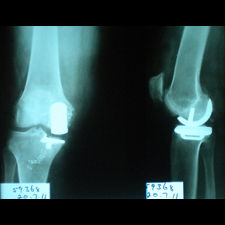

A 62 year old, female patient presented with a history of increasing right knee pain and loss of function over a 3-year period.

On clinical and radiological examination, she was assessed as having Medial Compartment Osteoarthritis. A uni-compartmental knee replacement was recommended and performed in June 2011. Patient has gone onto complete recovery with a satisfactory clinical outcome. She returned to independent function, six weeks after the surgery and now has a pain-free existence with full function in the right knee.